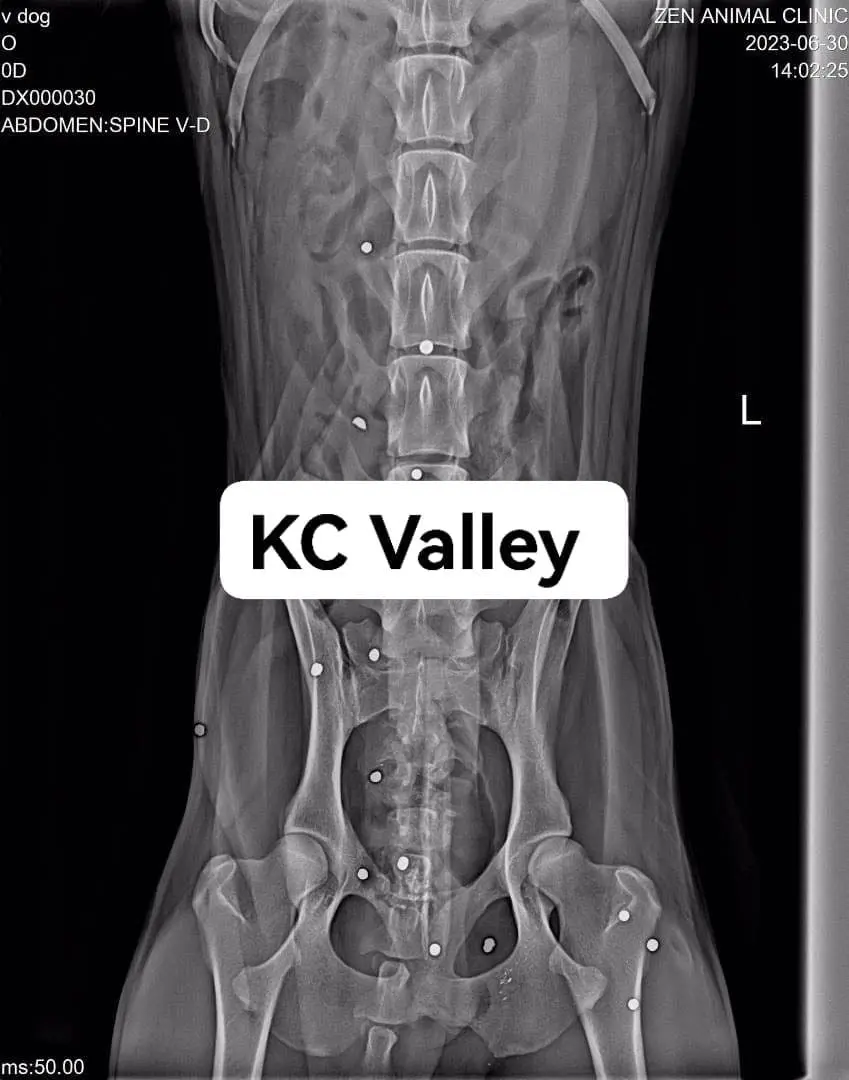

Unfortunately, a X-ray revealed that the dog had been shot more than 20 times with a BB gun and the bullets were still stuck inside its body, causing the wounds to fester.

As for the dog’s condition, KC Valley said that it was very weak and will stay under the vet’s care and remove the plastic bullets.